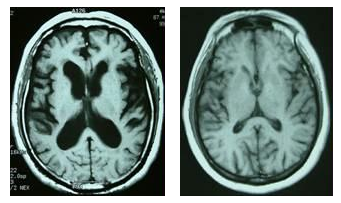

图1 左图为正常脑影像图,右图为阿尔茨海默病患者脑影像图 (二)病理诊断 目前,阿尔茨海默病诊断的金标准仍为病理检查。病理检查可见患者的大脑半球常呈对称性萎缩,脑沟变深,脑回变窄,侧脑室扩大。在对阿尔茨海默病患者的细胞学特殊检查中,除了可见老年斑和神经原纤维缠结外,还有神经元减少,神经轴索和突触的异常,星形细胞和小胶质细胞的反应以及脑血管的改变等等。